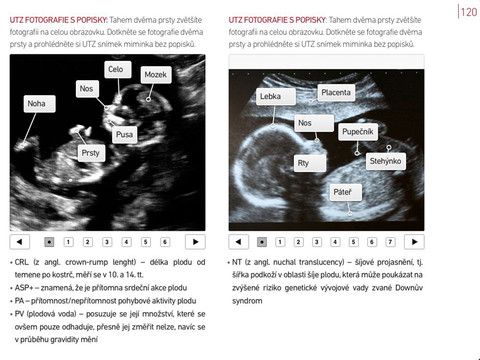

Videa natočená s předními českými lékaři vám přiblíží péči v průběhu těhotenství a zmírní vaše obavy z porodu. Díky názorné infografice a interaktivním popiskům se snadněji zorientujete v termínech vyšetření, výsledcích ultrazvuku nebo v kolonkách těhotenské průkazky. Kniha detailně ukazuje, jak se mění tělo těhotné ženy, jak se vyvíjí plod i co se děje uvnitř matčina těla.